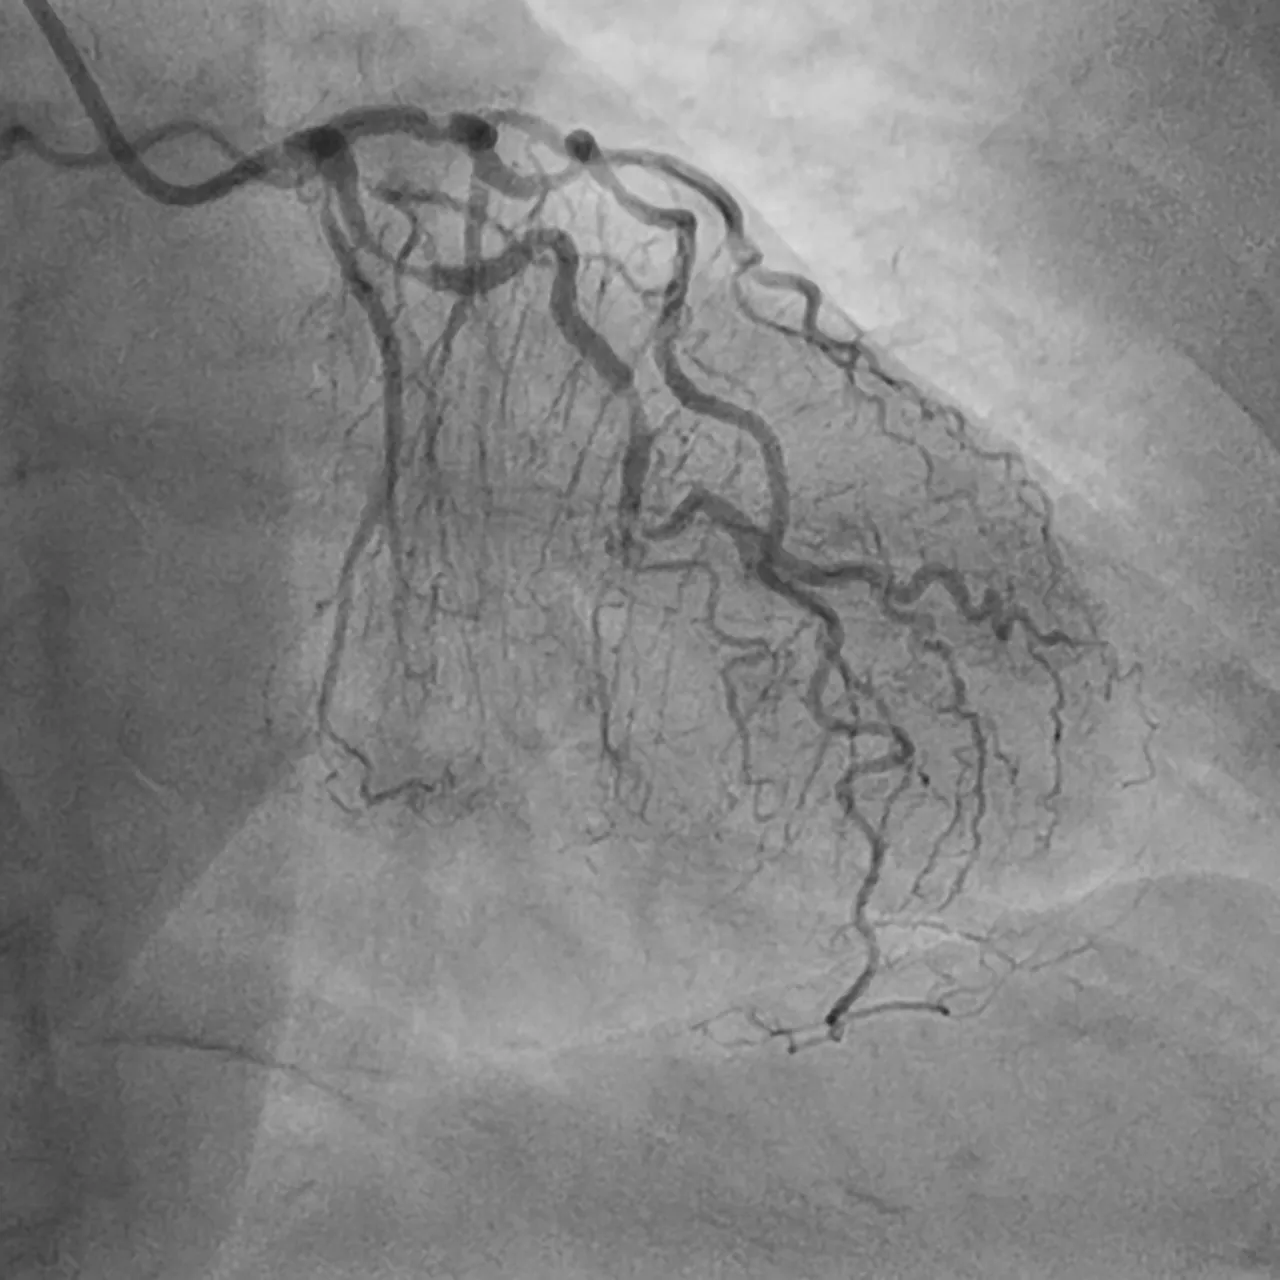

Coronary angiography is a medical procedure that uses a special contrast dye and X-rays to visualise the inside of the coronary arteries. This contrast dye is injected through a catheter – a thin, flexible tube inserted into an artery or vein. The dye illuminates the arteries during X-ray imaging, allowing for the detection of any blockages or narrowing. This information is crucial for diagnosing coronary artery disease (CAD), a leading cause of cardiovascular events.

• What to Expect During the Procedure Patients will receive a mild sedative to help them relax while remaining awake throughout the procedure. The doctor will then cleanse and numb the area where the catheter will be inserted using a local anaesthetic. Subsequently, a small incision is made, and the catheter is guided through an artery into the heart. Patients may experience dull pressure at the insertion site. After placing the catheter, the doctor injects a contrast dye and proceeds to take a series of X-ray images (angiograms) to monitor the flow of the dye within the coronary arteries and detect any blockages or constrictions of blood flow. The patient may feel a brief flushing sensation during the dye injection.